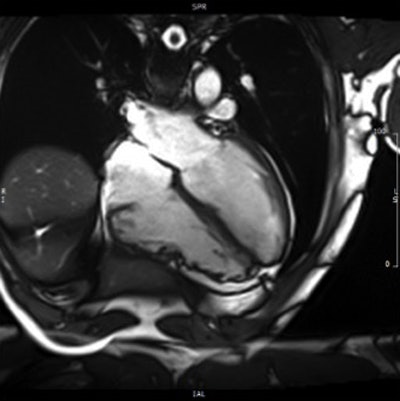

ARVC/D is a genetic heart disease usually transmitted via an autosomal pattern. Although it primarily involves the right ventricle, in rare cases it can encompass both sides of the heart. ARVC/D is typically characterized by partial or total absence of the right-ventricle musculature, which may be replaced by fibrofatty tissue, he said.

Amadu and colleagues from both institutions including Dr. C.L. Rodrigues, Dr. A. Dastidar, Dr. G.B. Meloni, Dr. M. Conti, Dr. Chiara Bucciarelli-Ducci et al, performed CMR on a 1.5-tesla scanner (Magnetom Avanto, Siemens Healthcare). A comprehensive protocol, including long and short-axis axial cine images and late gadolinium enhancement, was used in all patients.

In all, four of the 124 patients met the CMR criteria for ARCV/D. Of these, three had major criteria and one had minor criteria, for a prevalence of 3%.